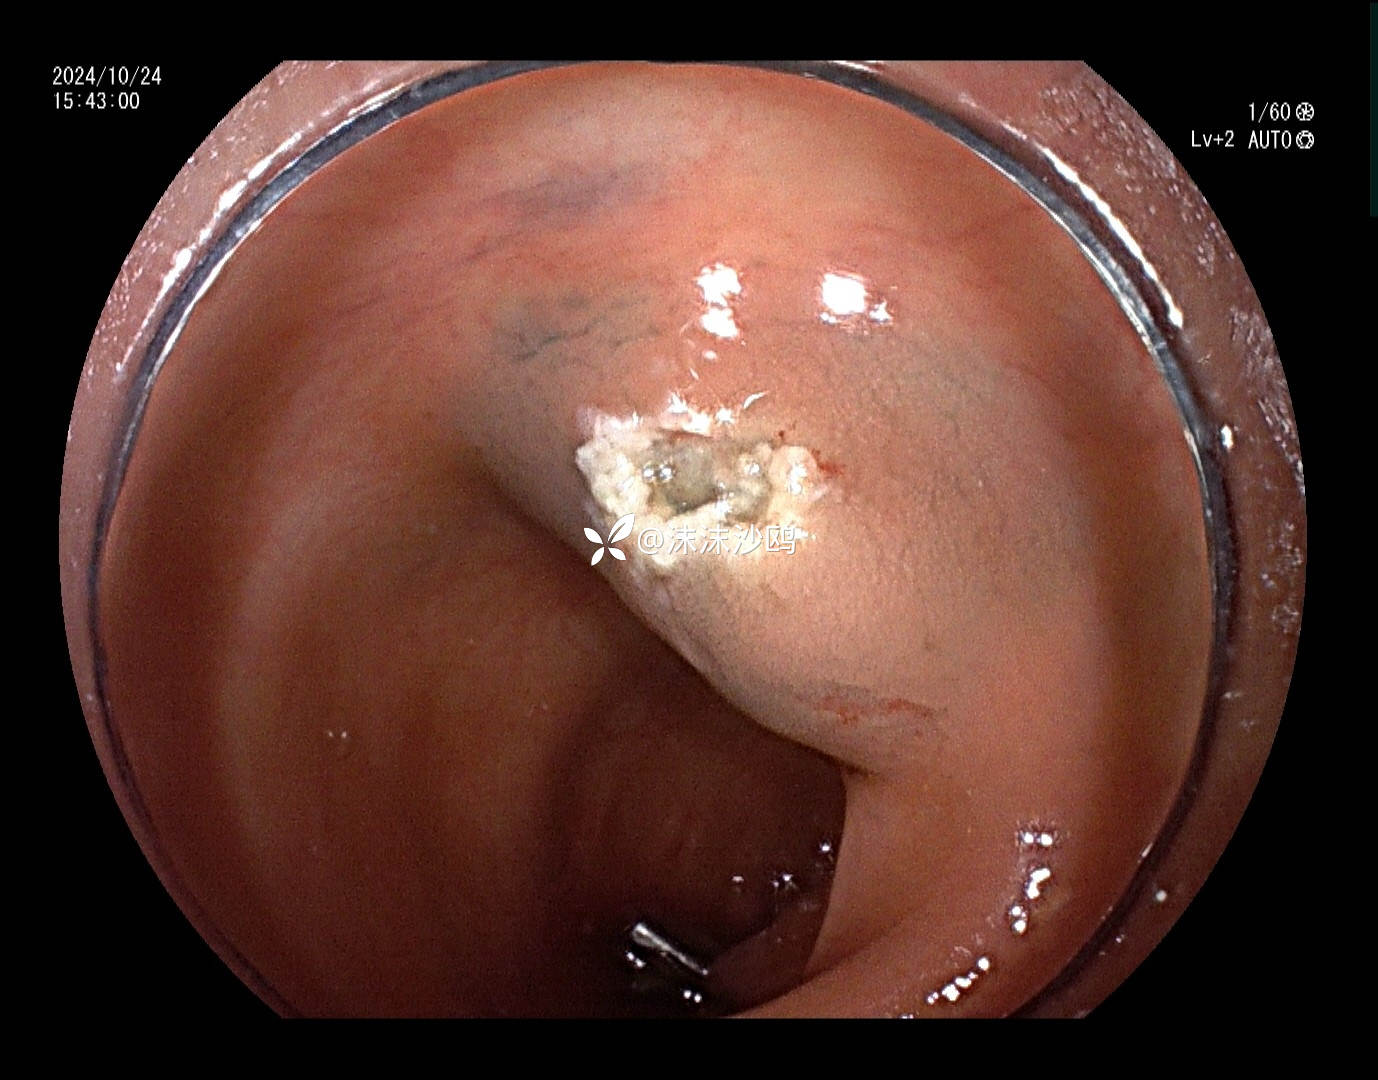

患者去年发现乙状结肠肿瘤同是发现多发腺瘤样隆起,先做了肿瘤切除手术,没有进一步放化疗,现来复查肠镜顺便嘎息肉。翻看之前的肠镜报告,肠道清洁差,发现的息肉就有六七个,应该还有漏掉的。嘱患者肠道一定要清洁到位。今日下午只安排了他一个人的肠镜专场,专门处理他的息肉。

冰山一角,大大小小嘎了十三四个,大的就有六七个,大部分EMR切除。希望术后不要有并发症。